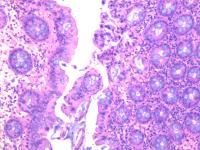

横结肠息肉

性别年龄56临床诊断

一般病史体检

标本名称横结肠息肉

大体所见灰白2粒

肠粘膜息肉。

小灶区域腺上皮有异型,重切一张再看看。

表面黏膜上皮有很少异型细胞。间质中一团上皮样细胞性质不明,没有明显异型性。可描述发报告。